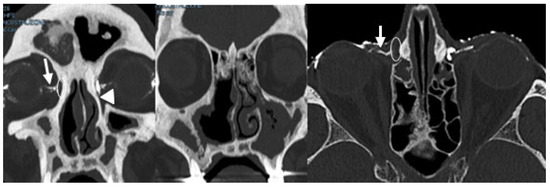

Background: Conventional CT–dacryocystography (CT-DCG) requires canalicular cannulation and forced contrast injection, which may distort anatomy and cause discomfort. This study describes a non-cannulated CT-DCG protocol using dropwise iodixano...